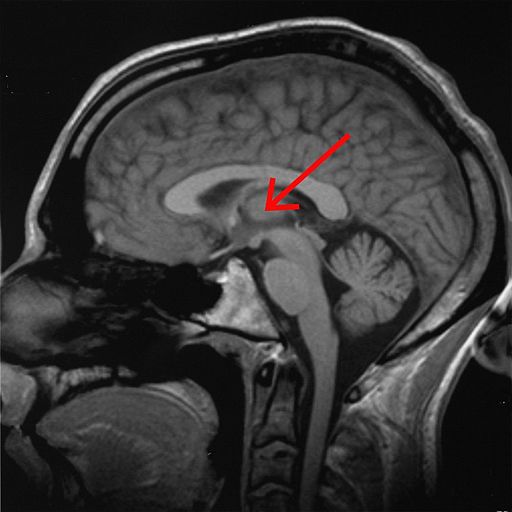

The thalamus (pl.: thalami; from Greek θάλαμος, "chamber") is a large mass of gray matter on the lateral wall of the third ventricle forming the dorsal part of the diencephalon (a division of the forebrain).

Thalamus je mozková struktura, která je součástí diencefala (mezimozek), a nachází se v blízkosti třetí mozkové komory. Má složitou strukturu, skládá se z řady jader a má komplexní funkce.

Thalamus – vejčitý útvar v diencefalu tvořící část stěny 3. mozkové komory. Přepojují se zde smyslové vjemy vč. bolesti vedené z periferie dále do mozkové kůry, z mozečku se do motorické kůry přepojují vzruchy důležité pro motoriku, další…

Thalamus (česky hrbol mezimozkový) je spolu s epithalamem součástí zadní části mezimozku (diencephalon) a je seskupením senzorických, asociačních a nespecifických jader. Zprostředkovává převod informací přicházejících z periférie do specifických projekčních a asociačních oblastí mozkové kůry a do důležitých center mozečku. Umožňuje také vzájemnou interakci vyšších oddílů CNS. Wikipedie